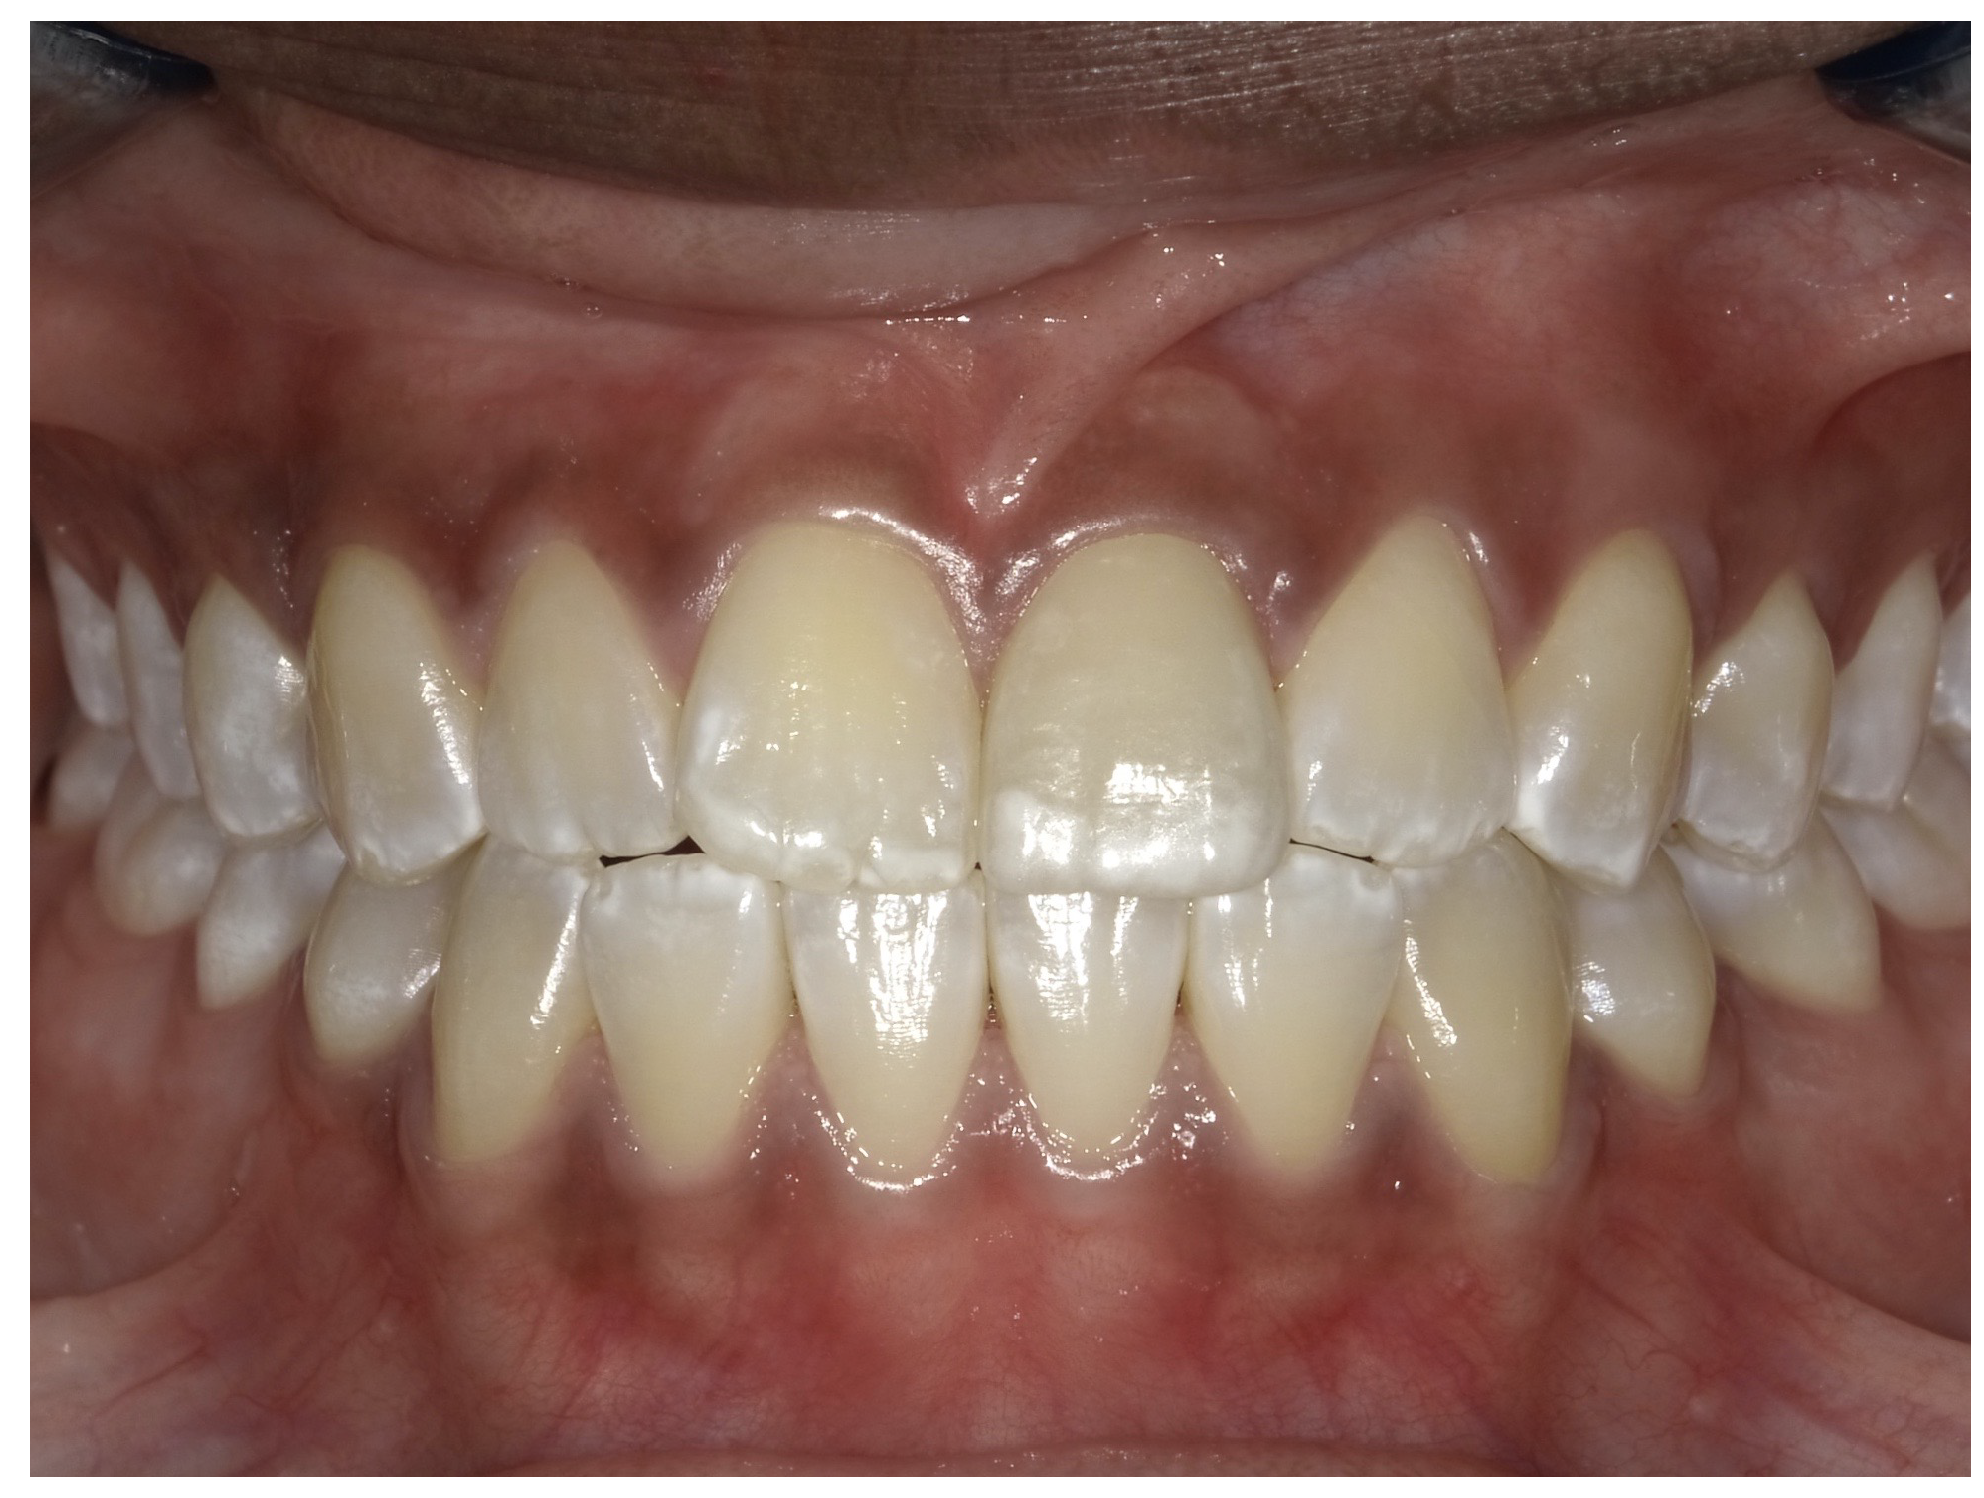

For the case in Figure 9 through Figure 11, the patent presented for an initial consultation with bonding completed on teeth Nos. 7 through 10 a few years prior with a chief complaint of not liking the way the resin bonding looked and how it was wearing. Up to this point, the bonding had repeatedly chipped and been repaired three times already. The patient's canines also exhibited signs of incised wear and flattening, which she did not like. Based on the patient's goals for her smile and her financial budget, she elected to have porcelain veneers completed on teeth Nos. 6 through 11. The total esthetics of the case design were somewhat limited given that the patient's esthetic zone included her posterior teeth and mandibular anterior teeth. Therefore, the color and characteristics of the veneers had to match her existing dentition closely.